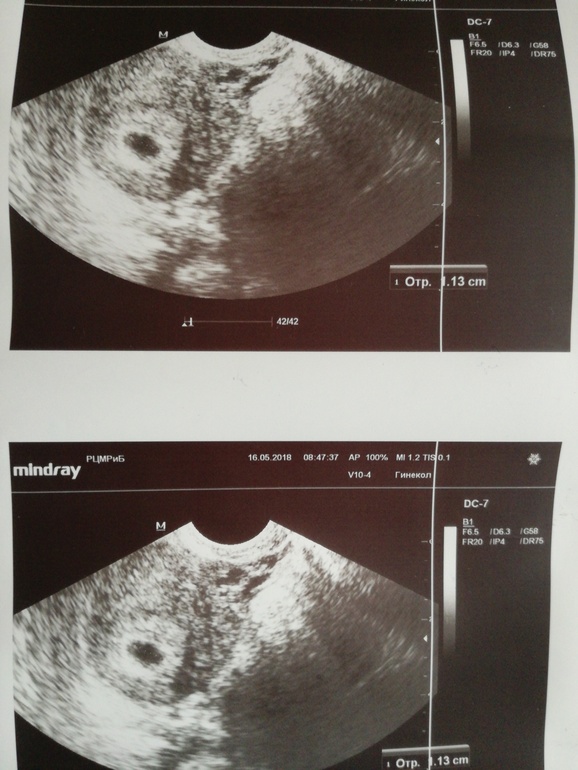

Беременность 5,3 недель узи

Вопросы про УЗИ, обследования и анализы: что, где, как, когда?Сделали сегодня узи, врач сказала все нормально - шестая неделя. На снимке пытаюсь разглядеть эмбриона)) вроде где левый плюсик он есть?))) и не большое ли плодное яйцо 1,13 см?

У меня в 5+1 пя было 16мм, в нем ничего тоже не было видно. Через 5 дней был явный желток и эмбрион около 4-5мм☺️ А пя было уже 21мм

Ничего не т в том что ещё ничего не видно. По сроку с 5.5 до 7 недель эмбрион может прятаться, как мне на УЗИ объясняли. Сходите в 6,5-7 точно все будет и малыш и сердечко)

Обычно на таком сроке ещё не виден эмбрион, а виден желточный мешочек. На этих фото малюсенький мешочек мы не разглядим)